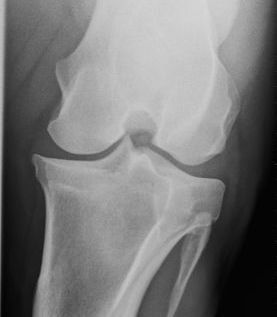

Digital radiography is used to view images of bone and soft tissue. The images are digital, rather than film and are available immediately, allowing for quick, on-site assessment of problems. The ability to manipulate the images on the computer and enhance specific regions of the image allows for better visualization of the problem areas.

Radiography is most commonly used in horses to view problems within the legs, making it an invaluable tool for lameness evaluations. Radiography is also very helpful in pre-purchase examinations, by helping uncover underlying or potential lameness issues before they manifest themselves symptomatically.